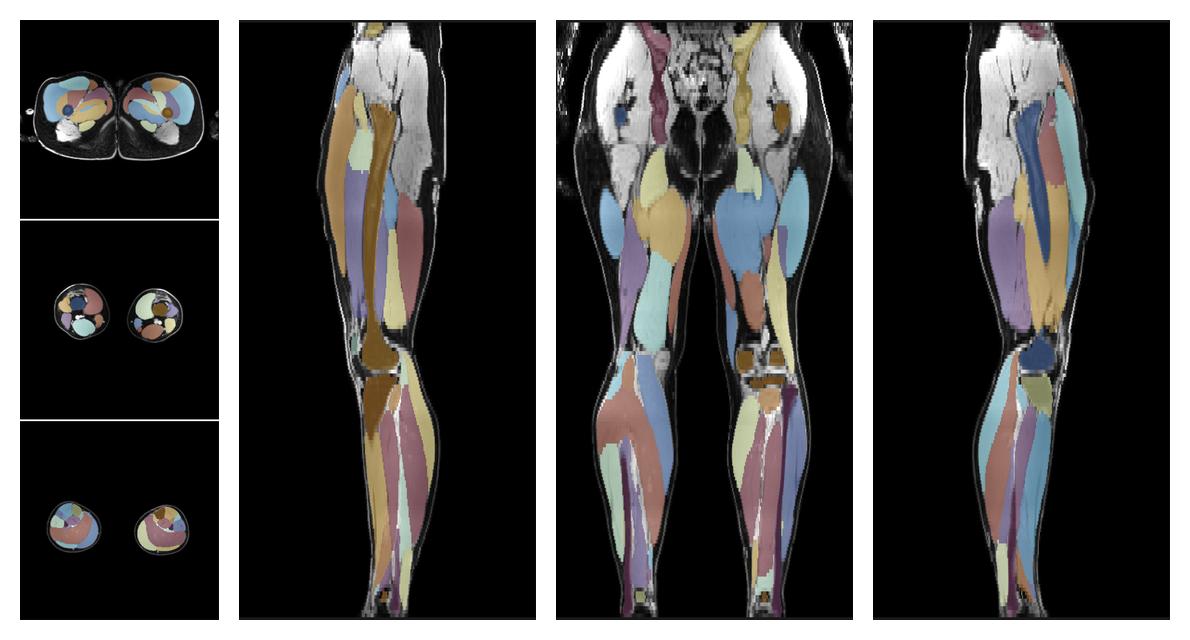

Muscle segmentation

Convolution neural network based (UNET) fiber automated muscle segmentation, for information look here».

• Automated muscle and bone segmentation.

Overlay of automated muscle segmentation labels on dixon water image.